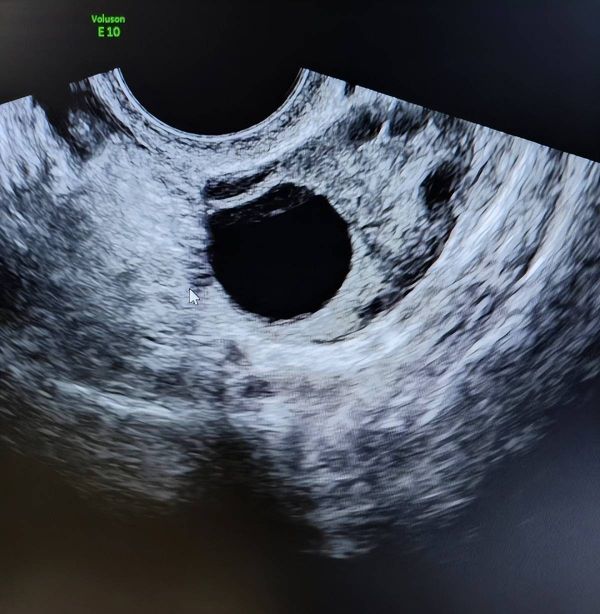

正常情况下,成熟卵泡直径一般在18~25mm之间。理想状态下,卵泡在超声影像中呈现为饱满、圆润的“小气球”。

做B超看到的图像,其实是这个“小气球”在某个切面上的投影。从不同角度看,它可能是很圆的,也可能是椭圆的,甚至有点不规则。但就像世界上没有两片完全相同的叶子,卵泡的形状也并非千篇一律。很多时候,卵泡会受到卵巢组织挤压、B超探头放的位置、测量角度等因素影响。只要大小达标、能正常排出,都属于正常现象。